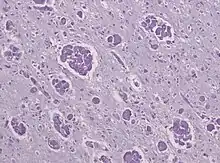

Krabbe disease

Like MLD, Krabbe disease is another type of leukodystrophy with autosomal recessive inheritance that is the result of a lysosomal storage disorder. It is due to a deletion in exon 16 of the GALC gene that causes a frameshift mutation leading to a premature stop codon. The GALC gene, found on chromosome 14 at position 31 (14q31), codes for the enzyme beta-galactocerebrosidase (GALC).[18] GALC is a lysosomal enzyme responsible for the catabolism of galactolipids, especially the toxic lipid psychosine, that are widely distributed throughout the brain. A deficiency in GALC thus causes a buildup of these fatty acids, leading to an incursion by cells called "globoid macrophages" that destroy oligodendrocytes, thereby inhibiting any further myelin formation.[19] Given the presence of globoid macrophages clustered near white matter, Krabbe disease often is called globoid cell leukodystrophy.